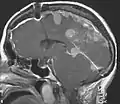

Un méningiome, tumeur bénigne des méninges, est présent dans environ la moitié des cas en intracrânien et au niveau de la moelle épinière dans un cinquième des cas[4]. Ils sont souvent multiples. Leurs manifestations dépendent de leurs tailles et de leurs localisations. Ils sont détectés par un scanner crânien ou une IRM. La présence de cette tumeur est corrélée avec un plus mauvais pronostic[9].

Les méningiomes sont, par contre, bien séparés des structures voisines et leur ablation chirurgicale ne pose pas de gros problèmes, sauf s'ils sont très proches de certaines structures cérébrales délicates d'accès ou fragiles (base du crâne en particulier, localisation qui correspond à l'émergence des nerfs crâniens[19]).